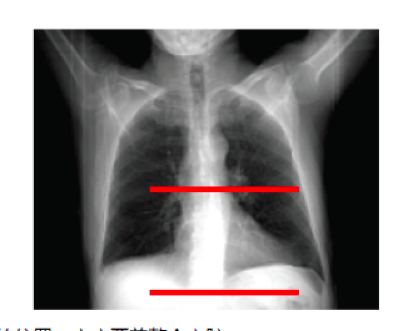

图1、扫描范围示例

扫描范围:扫描范围和剂量成正比关系,在保证解剖结构被完全覆盖时,尽量避免额外范围的无效扫描。 管电压(kVp):射线剂量和管电压的平方成正比关系,而图像噪声和管电压成反比关系,意味着管电压从120kVp降低到100kVp时,射线剂量会降低31%,而图像噪声增加20%。通常体重≤60kg或BMI≤22.5kg/m2的选择80kVp,体重≤90kg或BMI≤30kg/m2的选择100kVp(此阈值会因设备和审美指数略有不同)。 管电流(mA):射线剂量和管电流成正比关系,而图像噪声和管电流成线性反比关系,降低20%管电流,通常会降低20%射线剂量,但会增加12%的图像噪声。 螺距(pitch):心脏小螺距(0.2左右)重叠数据扫描是心脏螺旋扫描中剂量过高的原因,螺距和剂量成反比关系,螺距增加2倍,剂量降低50%。但在心脏扫描模式下,螺距和噪声没有一定的相关性。